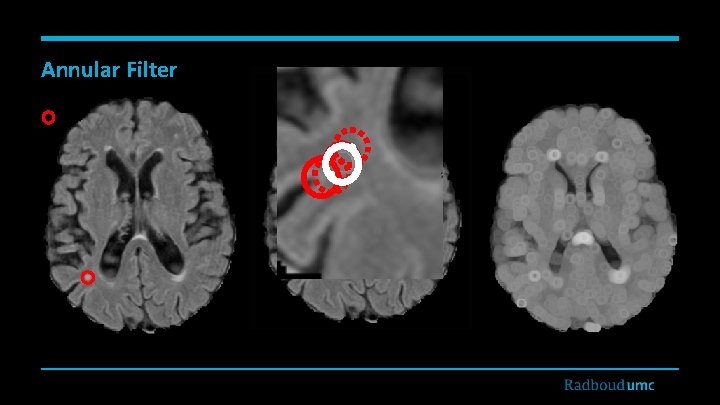

Annular Filter

Features • • • Intensities • FLAIR • T 1 • T 2* Location • X, Y, Z in the MNI space • Distances from • Brain surface • Left & right ventricles • Midsagittal brain surface • Prior probability based on location Tissue probabilities • WM probability • GM probability • CSF probability Second order derivatives • Multiscale Laplacian of Guassian • Multiscale determinant of Hessian matrix • Vesselness Multiscale grayscale annular filter

Results: FROC (Different Feature Sets) I: Intensities T: tissue probabilities L: Location features S: Second order derivatives A: Annular filter

Discussion and Conclusions • • • Detection of small WMLs is a challenging task. • Partial volume effect • Dirty white matter • Patient movement artifact and noises Contribution of features • Location information • Annular filter Contribution of classifier • Adaboost